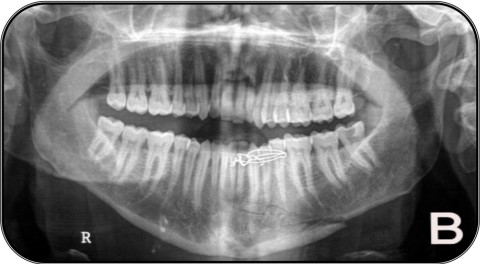

Extra-oral MultiDirectional Distractor: A Multi Uses Distractor